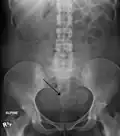

Two calcified fibroids (in the uterus)

-